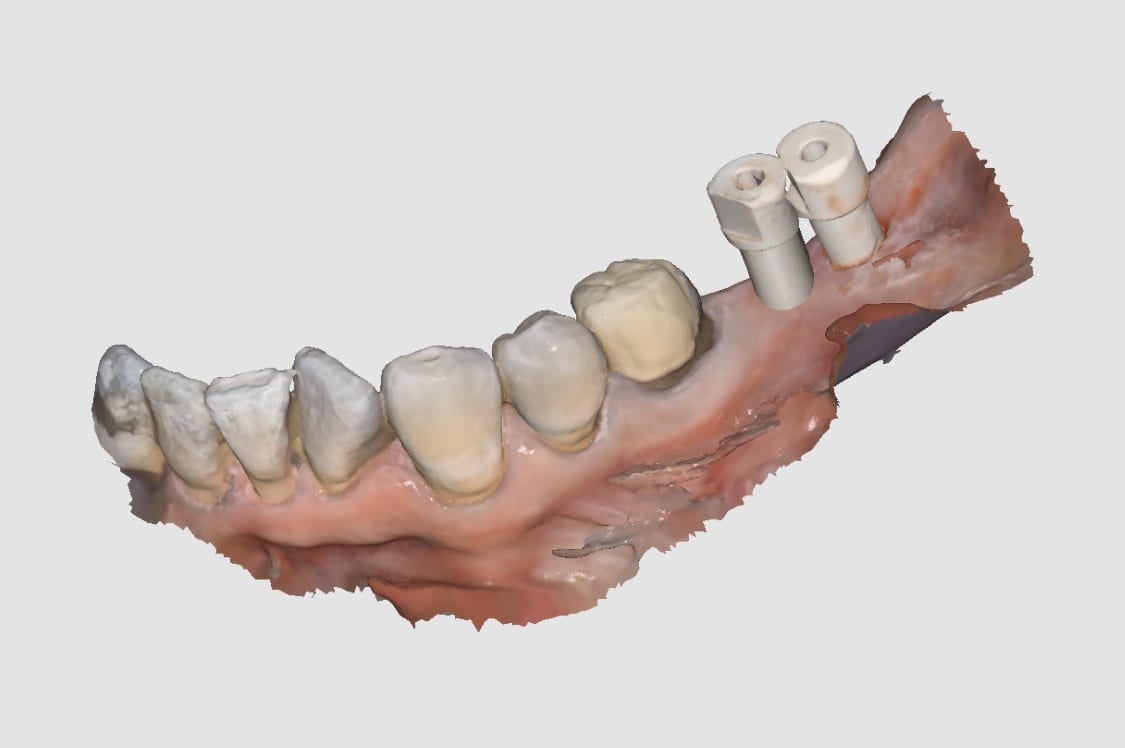

“Yes it can

I would however do separate abutments and crowns just in case you bind somewhere you can adjust crowns separate from abutments

You would have struggle with analog impressions

This is THE indication for digital dentistry over analog impressions!

I’m stealing this photo for my presentations 😉”